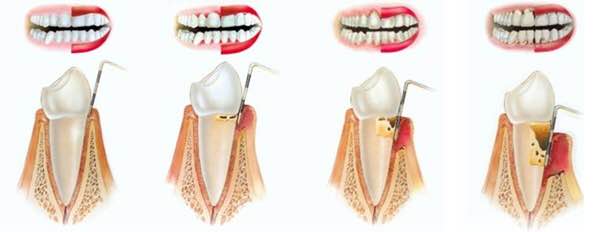

fogszuvasodás kezeléseSzájüregünkben, a fogak felszínén, az ínyen, a nyelvünkön számos baktérium található, melyek fontos szerepet játszanak a biológiai egyensúly fenntartásában. Néhány baktérium azonban a táplálkozásunk során elfogyasztott szénhidrátot képes lebontani úgy, hogy közben sav keletkezik. Ennek következménye, hogy étkezés után csökken szájüregünk pH-értéke, azaz savas közeg alakul ki, amelyet nyálunk semlegesítő hatása egy idő után helyreállít. Abban az esetben, ha gyakran fogyasztunk szénhidráttartalmú ételeket, nincs idő, hogy a savak semlegesítődjenek, ezért hosszan tartó alacsony pH-jú időszakok alakulnak ki, s elkezdődik a fogszuvasodás.

Fogaink külső felszínét szervezetünk legkeményebb anyaga, a zománc borítja. A zománc 98%-át szervetlen anyagok alkotják, amelyek savhatásra képesek kioldódni. Ez a magyarázata annak, hogy egy ilyen kemény anyag képes meggyengülni, sőt üreg képződhet pusztán baktériumok és szénhidrát hatására. Abban az esetben, ha a kórokozók átjutottak a zománc rétegen, a fogszuvasodás terjedése felgyorsulhat , ilyenkor általában már panaszos a fog, hidegre, édesre intenzívebben reagál.